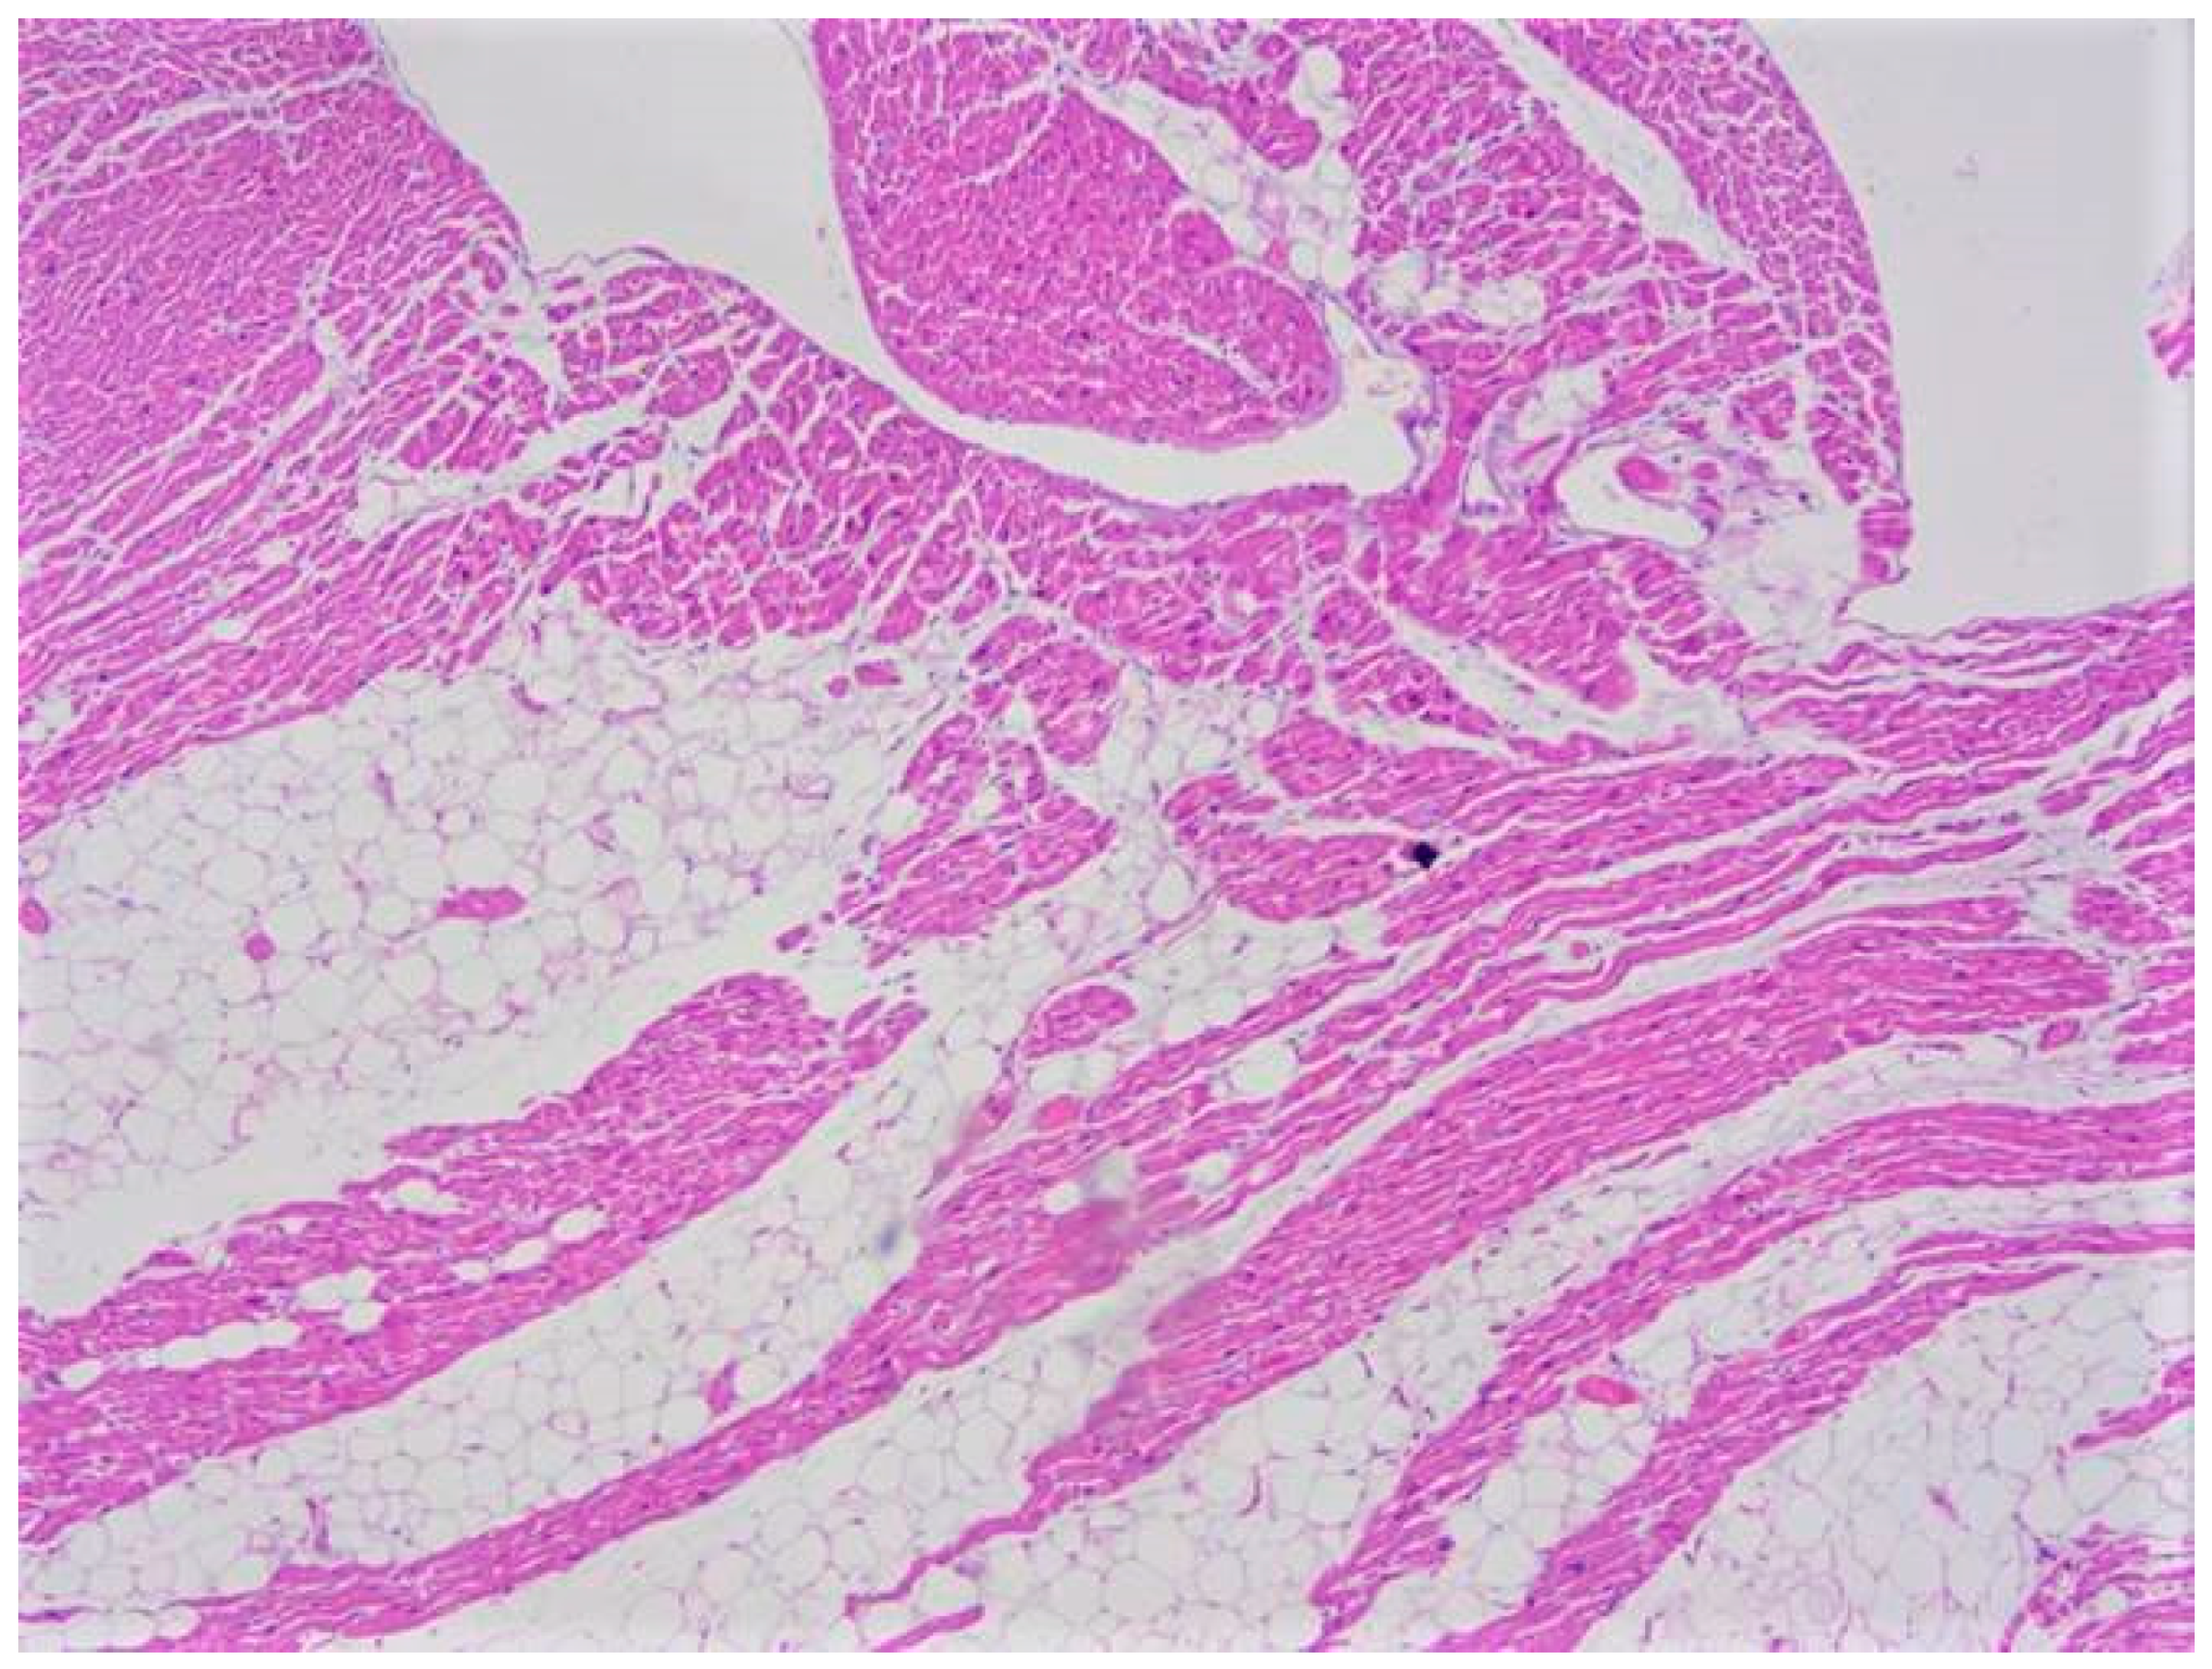

| Typical histopathological features | Myocytes hypertrophy, disarray, thickened intramural arterioles with luminal narrowing, myocardial fibrosis [102,103] | Fibrofatty replacement of the ventricular myocardium with a subepicardial-mid-mural or transmural distribution [54] | Replacement fibrosis, interstitial fibrosis, atrophied and/or hypertrophied cardiomyocytes, nuclear pleomorphism [82] |